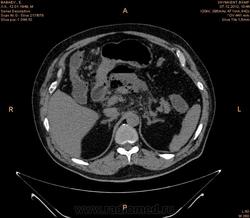

Здравствуйте , коллеги.Помогите пожалуйста разобраться.Больной мужчина 65 лет поступил с диагнозом Хр.панкреатит.Мех.желтуха. Эфгдс : Язва желудка.Хр.панкреатит. КТ - зак : Свободный газ в брюшной полости.Разрыв полого органа.Гиподенсные зоны с плотностью -827 ед.н., 937,0 ед.Н. Я оценила как свободный газ. На операций сказали Жировой панкренкроз. Больной умер.Неужели я ошиблось.

Если Вы имеете в виду гипозоны в проекции поджелудочной железы, то Вы ошиблись. Это редкий вариант панкреонекроза, эмфизематозный (острый некротический панкреатит)

Не очень редкий. Цитата: "Я оценила как свободный газ."  Как бы не видно "свободного" газа, он чем-то ограничен на всех срезах. Т.е. газовая дегенерация "чего-то", но не полого органа. Видимо в данном случае парапанкреатической клетчатки. При операции это никто из хирургов не видит, т.к. там есть и жидкость и кровь и только нами видимый газ.

поджелудочная диффузно увеличена ,в области тела определяется гиподенсивный относительно паренхимы поджелудочной железы  участок  с распространением в переднее параренальное пространство,преймущественно слева ,с включениями мелких пузырьков газа(инфицированный панкреонекроз),причем эпицентр имеет связь с вирсунговым протоком (разрыв ) с переходом процесса в брюшную полость.не исключал бы в данном случае и наличие желудочно-кишечного свища ,что может  иметь место  при таких изменениях.а так на первый план эмфизематозный(инфицированный панкреонекроз) острый панкреатит